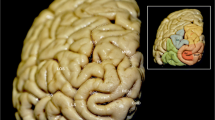

The inferior frontal gyrus (IFG) consists of orbital, triangular and opercular parts in the anteroposterior direction. The POP is separated from the PG by the inferior precentral sulcus (IPS), from the middle frontal gyrus by the IFS and from the PTR by the anterior ascending ramus (AR) of SF. The PTR is separated from the POP by the AR, from the middle frontal gyrus by IFS, and from the pars orbitalis (POR) by the anterior horizontal ramus (HR) of the SF. Occasionally, a sulcus between the AR and IPS exists in POR that can be easily distinguished from the AR and termed the ‘diagonal sulcus’ (DS) [39]. Likewise, the PTR includes ‘triangular sulcus’ (TS). These sulci were defined to separate PTR and POP from the neighboring cortical structures [14, 26, 27] and used as the anatomical boundaries of these regions [26, 27, 39, 40] in this study (Fig. 1).

Major sulci defining the borders of the pars opercularis, triangularis and orbitalis. a aSCS: anterior subcentral sulcus (blue line), AR ascending ramus of the sylvian fissure (purple line), CS central sulcus (red line), DS diagonal sulcus (pink line), FMS frontomarginal sulcus (brown line), FOS frontoorbital sulcus (orange line), HR horizontal ramus of the sylvian fissure (purple line), IFS inferior frontal sulcus (black line), IPS inferior precentral sulcus (white line), SF sylvian fissure (purple line), TS triangular sulcus (green line). b POP: pars opercularis (the area within the confines of the yellow line), POR pars orbitalis (the area within the confines of the blue line), PTR pars triangularis (the area within the confines of the pink line) (color figure online)